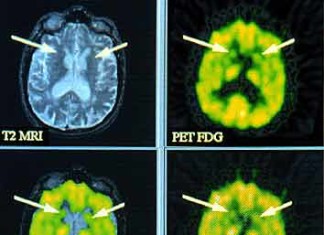

Sobre expresión de la enzima reguladora puede proteger la neurodegeneración...

El tratamiento que aumenta los niveles cerebrales de una enzima importante de regulación puede reducir la pérdida de células cerebrales que caracteriza a la enfermedad de Huntington (HD) y otras enfermedades neurodegenerativas. En un informe...